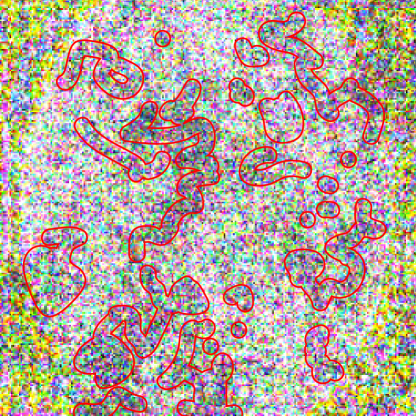

While imperceptible in the final images, the perturbations for dermatoscopic and fundoscopic images were found to carry easily perceptible information about the source image, when the changes were scaled to a range of [0,255]0255[0,255]. In these cases, the adversarial “noise” contained the shape of the lesion or eye. For dermatoscopic images, this shape was in the form of a densely perturbed ring enclosing a sparsely perturbed center (Fig. 8(a)). This phenomenon was most visible when ϵ=0.00125italic-ϵ0.00125\epsilon=0.00125. For the fundoscopic images, this shape was represented by a sparsely perturbed ellipse. In the attacks generated for the model with attention, the shape of this ellipse occasionally diverged from the true shape of the eye (Fig. 8(b)).

(b) Divergence from shape of eye